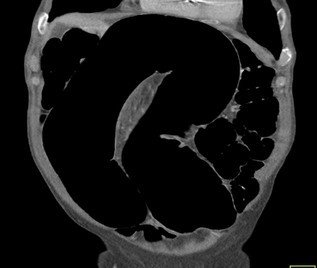

Abdominal CT images

Large gas-filled loop without haustral markings, forming a closed-loop obstruction

Beak sign: Progressive tapering of afferent and efferent limbs leading into twist